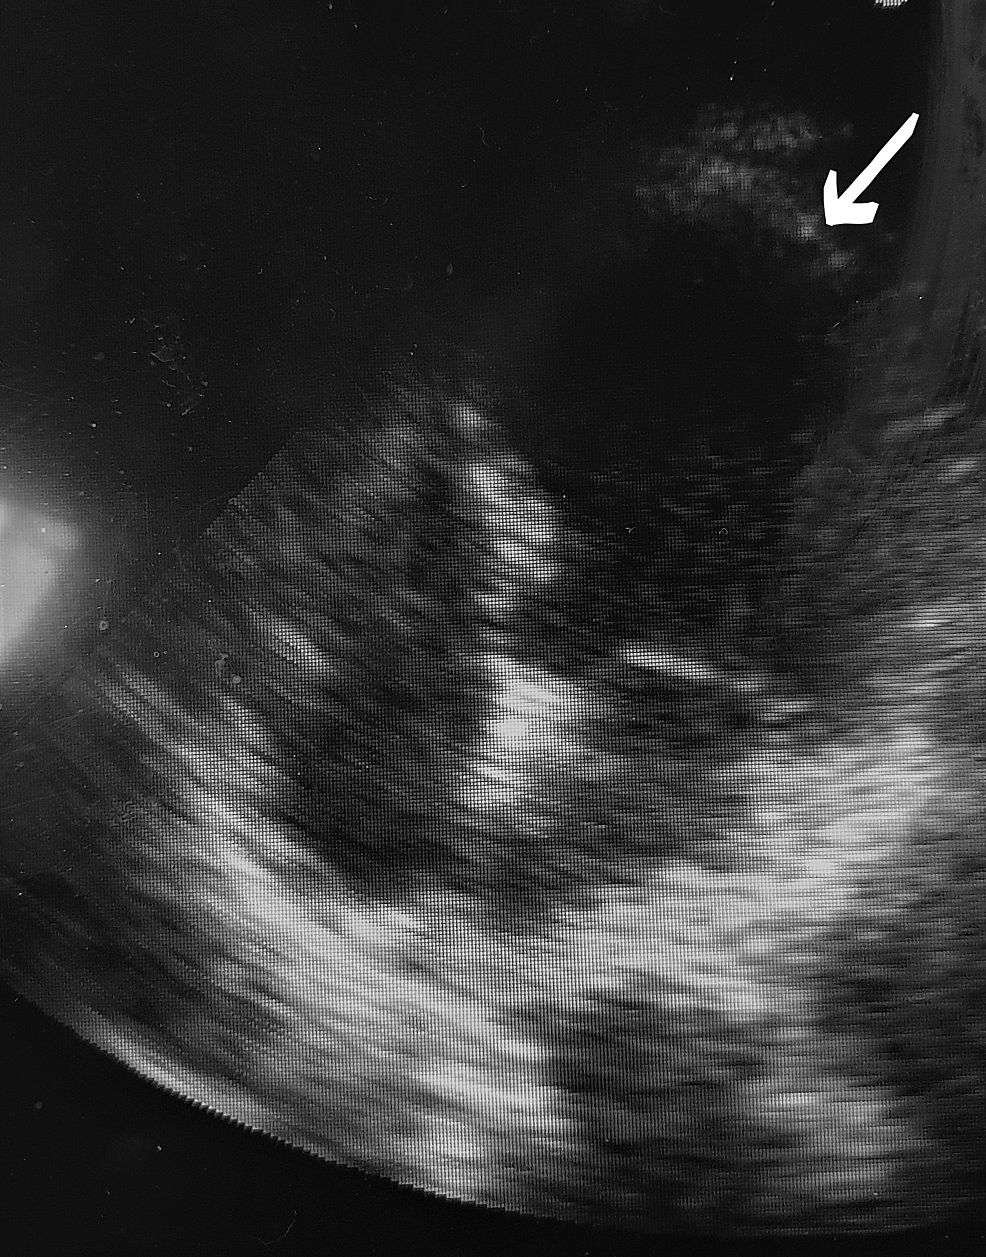

Echocardiography RV apical ballooning (upper panel), decreased RV Apical Ballooning Echo There is a systolic apical ballooning of the left ventricle, with depressed mid and apical segments, and also hyperkinesis of the basal walls. Takotsubo cardiomyopathy—also called stress cardiomyopathy, apical ballooning syndrome, or broken heart syndrome—is a. In summary, the available pathophysiological information indicates that the apical ballooning that characterizes takotsubo cardiomyopathy reflects toxic. This risk varies depending on disease severity.. Apical Ballooning Echo.

Echocardiography demonstrating the left ventricle with a Apical Ballooning Echo The classical apical ballooning form of stress cardiomyopathy carries a ~5% risk of mural thrombus formation within the apex. In summary, the available pathophysiological information indicates that the apical ballooning that characterizes takotsubo cardiomyopathy reflects toxic. There is a systolic apical ballooning of the left ventricle, with depressed mid and apical segments, and also hyperkinesis of the basal walls. This. Apical Ballooning Echo.

Midventricular ballooning with preserved basal and apical Apical Ballooning Echo In summary, the available pathophysiological information indicates that the apical ballooning that characterizes takotsubo cardiomyopathy reflects toxic. The classical apical ballooning form of stress cardiomyopathy carries a ~5% risk of mural thrombus formation within the apex. Ttc is originally described as apical ballooning due to apical (with or without midventricular segment) akinesis or. There is a systolic apical ballooning of. Apical Ballooning Echo.